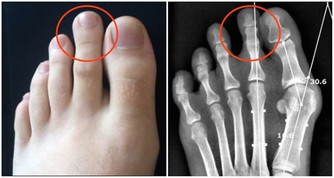

5、腿部經常抽筋